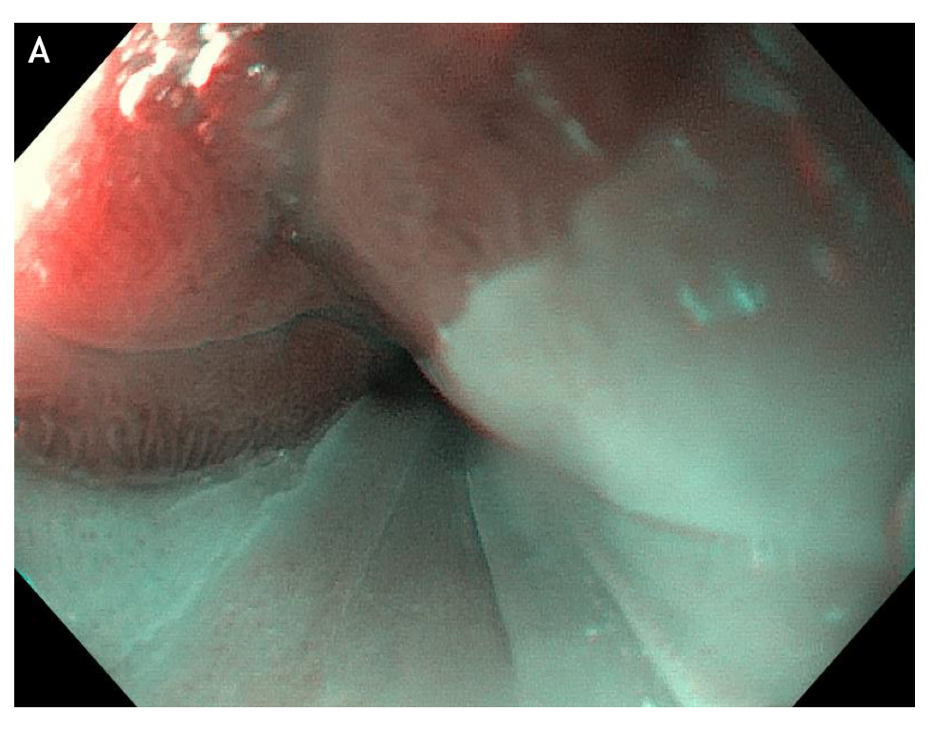

Figure 5 large areas of resected tissue and multiple lesions were independent predictors of stricture formation. A: Three areas of cervical inlet patches, with kissing distribution, in a middle age women with uterine cancer history, presenting for reflux complaints and globus sensation. Detailed image in (B) white light endoscopy and (C) narrow band imaging. D: Irregular Z line in the same patient suggesting concomitant gastroesophageal reflux disease.